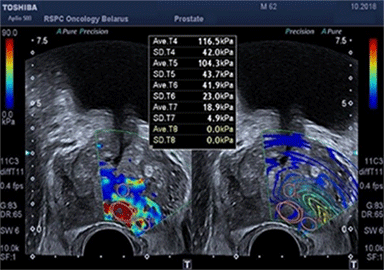

Существующие стандартные методы диагностики злокачественных опухолей предстательной железы обладают высокой точностью при выявлении заболевания. В РНПЦ ОМР им.Н.Н.Александрова используются и новые методы исследования, позволяющие улучшить стандартный подход на основе применения трансректального ультразвукового исследования с эластографией сдвиговой волны, которая открыла новые возможности количественной оценки жесткости ткани и позволяет определить локализацию подозрительных очагов.

Для подтверждения или исключения наличия злокачественной опухоли предстательной железы выполняется биопсия под контролем трансректального ультразвукового исследования. Она состоит из целевого этапа получения материала из подозрительных очагов, которые выявлены при помощи мультипараметрической МРТ таза и трансректального УЗИ с эластографией сдвиговой волны (т.к. точность определения диагноза возрастает, когда биопсия ориентирована на более жесткие области) и рекомендуется в сочетании с систематическим многоточечным этапом по определенной схеме.

Эластография показывает преимущества при выявлении в области верхушки и средней части простаты, тогда как МРТ – в визуализации базальной и переходной зон.

На рисунке представлен клинический пример пациента с повышенным уровнем ПСА. Ему выполнены мультипараметическая МРТ и трансректальное УЗИ с эластографией сдвиговой волны по данным которых определялись подозрительные очаги (указано стрелками или красным цветом). В последующем выполнена биопсии предстательной железы, которая состояла из систематического и целевого этапов. По результатам биопсии установлен диагноз рак предстательной железы с суммой баллов Глисона 4+3 (ISUP Grade 3). Пациенту выполнена радикальная простатэктомия в результатах которой подтвердилась правильно установленная стадия и лечение проведено успешно.

Установившийся тренд на изменение подходов к методике выполнения биопсии предстательной железы с включением целевого этапа при проведении систематической биопсии является результатом определенных успехов развития методов лучевой диагностики, в частности совместного использования при планировании биопсии результатов мультипараметрической МРТ и трансректального УЗИ с эластографией сдвиговой волны.